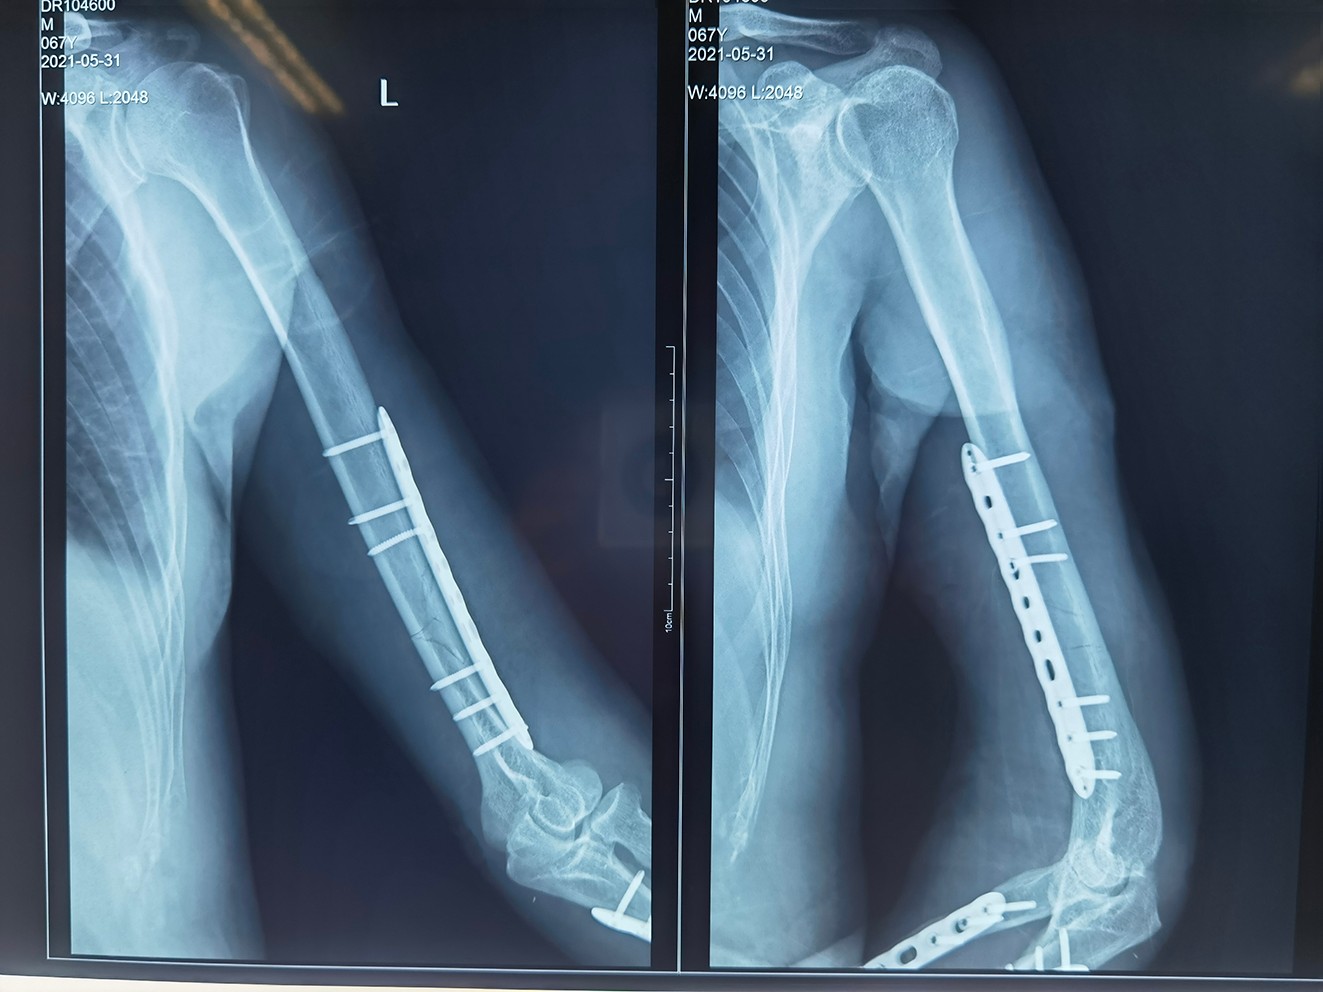

11點05分,G先生被送往手術(shù)。由于患者斷端組織損傷大,部分組織已經(jīng)壞死或缺損、血管、神經(jīng)損傷嚴(yán)重,大大增加了再植的難度。同時,麻醉科團隊第一時間對患者實施麻醉。由骨科專家宋杰主任、楊勝相院長、張廣院長三位大咖級專家組成的手術(shù)團隊,立馬對患者進(jìn)行清創(chuàng)、修整、固定。

微信截圖_20210601175510.png

宋杰主任道:“斷端組織損傷實在太嚴(yán)重了。在保住患者生命和不截肢的前提下,我們要盡全力讓斷臂恢復(fù)生機!”時間一分一秒過去,手術(shù)團隊在和時間賽跑,全員凝心聚神,沒有一絲松懈。術(shù)中,陸續(xù)聽見手術(shù)團隊興奮的喊:“骨骼完成連接、血管順利再通、斷裂的神經(jīng)、肌肉和肌腱吻合成功。”

宋杰主任介紹道:經(jīng)過全體醫(yī)護(hù)人員的高度重視和精心護(hù)理下,G先生順利度過危險期,轉(zhuǎn)入普通病房進(jìn)行治療。目前術(shù)后兩周,斷離的左臂也已確定完全接活。待部分壞死皮膚愈合良好、肌腱、肌肉愈合,就可以康復(fù)醫(yī)生指導(dǎo)和幫助下做一些主動及被動康復(fù)鍛煉,等患者掌握方法就可出院了